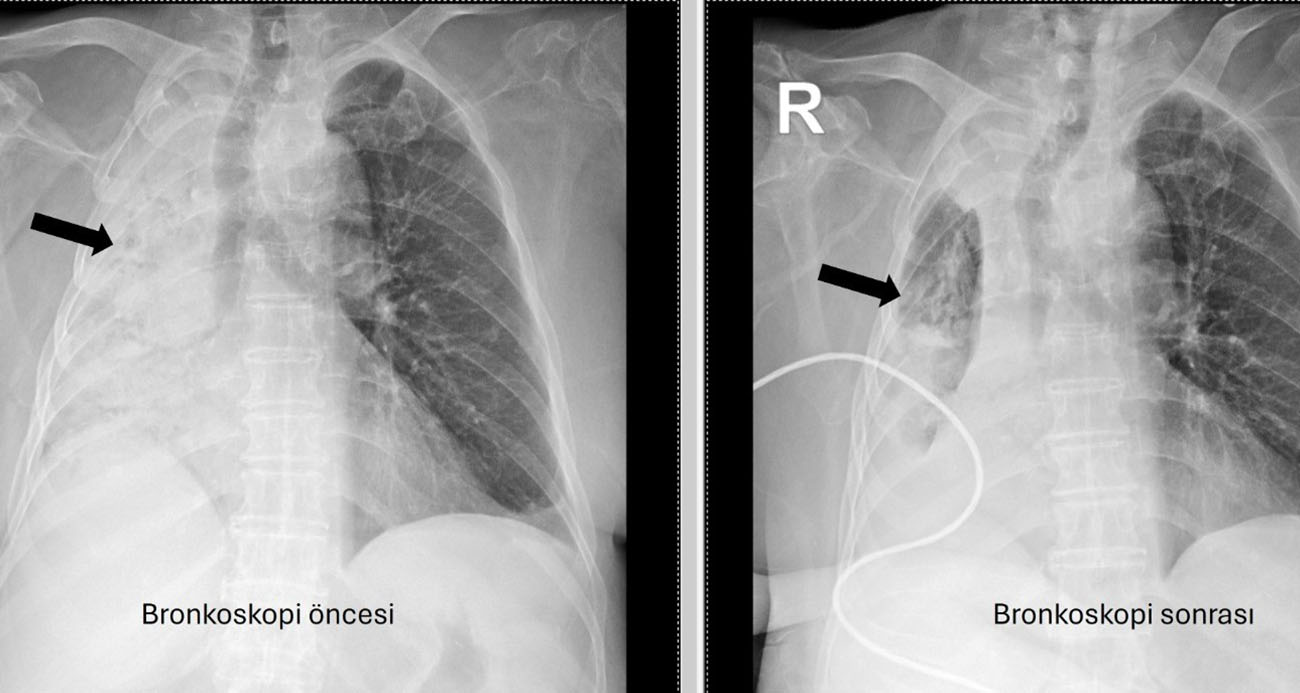

Denizli’de yaşayan ve emekli öğretmen olan 78 yaşındaki felçli kadın son zamanlarda sık sık akciğer enfeksiyonu nedeniyle hastaneye gidiyordu. 1 ay önce gittiği hastanede bronkoskopi yapılmasına rağmen sorun saptanmadığı öğrenildi. Yaşlı kadının son gittiği hastanede sağ akciğerinin tamamen kapandığının tespit edilmesi üzerine Pamukkale Üniversitesi Hastanesine başvuruldu. PAÜ Hastaneleri Göğüs Hastalıkları Anabilim Dalı Öğr. Üyesi Prof. Dr. Göksel Altınışık Ergur, tarafından yapılan tetkiklerde sağ akciğere giden hava yolunun bütünüyle kapalı olduğu görüldü. hastaya acil bronkoskopi planlanıp hemen işlemin gerçekleştirildiğini söyleyen Prof. Dr. Altınışık Ergur, "Fleksibl (esnek, eğilip bükülebilir) bronkoskop ile hava yolları incelenirken çok yoğun ve koyu sekresyon olduğu, bunun iyice temizlenmesi sonucunda ancak hava yollarının incelenebileceği görüldü. Aspiratör (içerideki salgıları emmeye yarayan bir cihaz) sayesinde hava yollarına steril sıvı verilip emilerek bu temizlik yapıldı. Sonrasında sağ akciğere giden hava yolunda sarı bir nesne olduğu görüldü. Bu hâliyle yabancı cisim olduğu anlaşıldığı gibi bunun mısır tanesine benzerliği de açıktı. Yabancı cismi çıkarma işlemi genel anestezi altında, rijit bronkoskop ile yapılmak üzere planlanabilirdi; çünkü bu durumun tedavisi yabancı cismin oradan, ek sorun oluşturmaksızın çıkarmaktı. Ancak, genel anestezi altındaki bir işlem için hastanın genel durumu bozuk olduğundan, özellikle ek hastalıkları ve enfeksiyon varlığı ile işlem riski artacağından hastadaki cismin fark edildiği sırada çıkarılmasına şans vermek daha uygun görüldü. Hava yolu içindeki sıvıları emen aspiratörün gücünü kullanılarak cismin çıkarılması mümkündü. Bronkoskobun ucu, sarı cismin gövdesine dayanıp aspiratör ile emme sayesinde ikisi birbirine sımsıkı yapıştırıldı. Emme gücünün azaltılmamasına dikkat ederek yabancı cisim ve bronkoskop, aynı zamanda hava yollarından dışarıya başarı ile çıkarıldı. İşlem sonrasında hasta yakınına mısır tanesi açısından tıbbi öykü yeniden sorulduğunda, hastamızın bundan beş ay önce yediği pizzanın üzerinde mısır taneleri olduğu öğrenildi. O sırada ani bir yakınma ortaya çıkmadığı için böyle bir ihtimal akla gelmemişti. Düşkün hastalar taneli gıdalar yerken, bu durumun fark edilmeden de gelişebileceğini göstermesi açısından önemli olan bu tablo, hastaların bir dedektif titizliği ile değerlendirilmesi gerekliliğini bir kez daha ortaya koymaktadır" dedi.